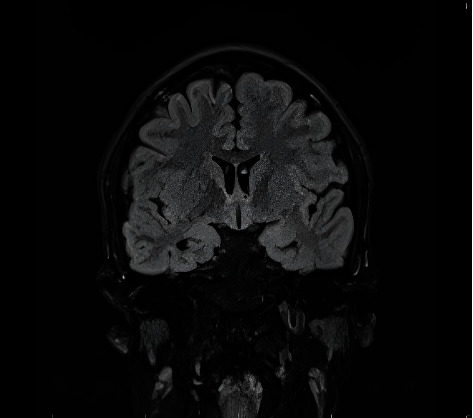

An 18-year-old male presented with new-onset focal to bilateral tonic-clonic seizures 5 days after receiving the first dose of COVID-19 vaccine. 3 days later, an identical seizure occurred lasting 1 min, leading to an acute presentation to the hospital. In hospital, the patient was loaded with intravenous phenytoin and started on levetiracetam with no further seizure recurrence. CT venogram and scalp EEG were unremarkable. MRI brain revealed generalised atrophy with mild bilateral hippocampal atrophy. The patient was maintained on 500 mg levetiracetam twice daily and advised to proceed with subsequent doses of vaccination. Vaccinations have been associated with breakthrough seizures. In this case, COVID-19 vaccination possibly unmasked an underlying predisposition for epilepsy.

Abstract Image